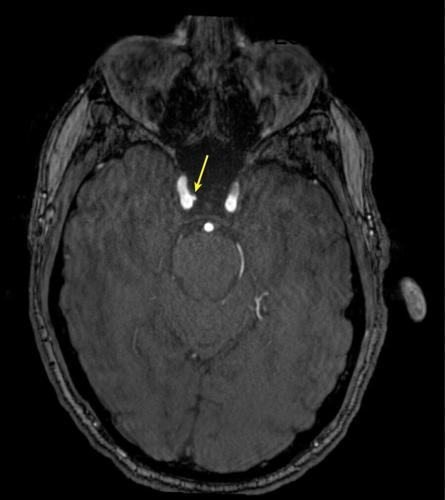

Representative axial time-of-flight MR angiography image in a 35-year-old male participant shows a medially projecting intracranial aneurysm (arrow) originating from the right cavernous segment of the internal carotid artery. (RSNA via SWNS)

Aneurysm prevalence was greater in the high-exposure group (9.5%) compared to the low-exposure group (2.7%).

De Giorgi said: "Intracranial aneurysms were three times more common in highly exposed personnel.

"Even after accounting for other health factors such as age and blood pressure, the association remained significant.

"These findings suggest that repeated blast exposure may leave a measurable vascular signature in the brain."